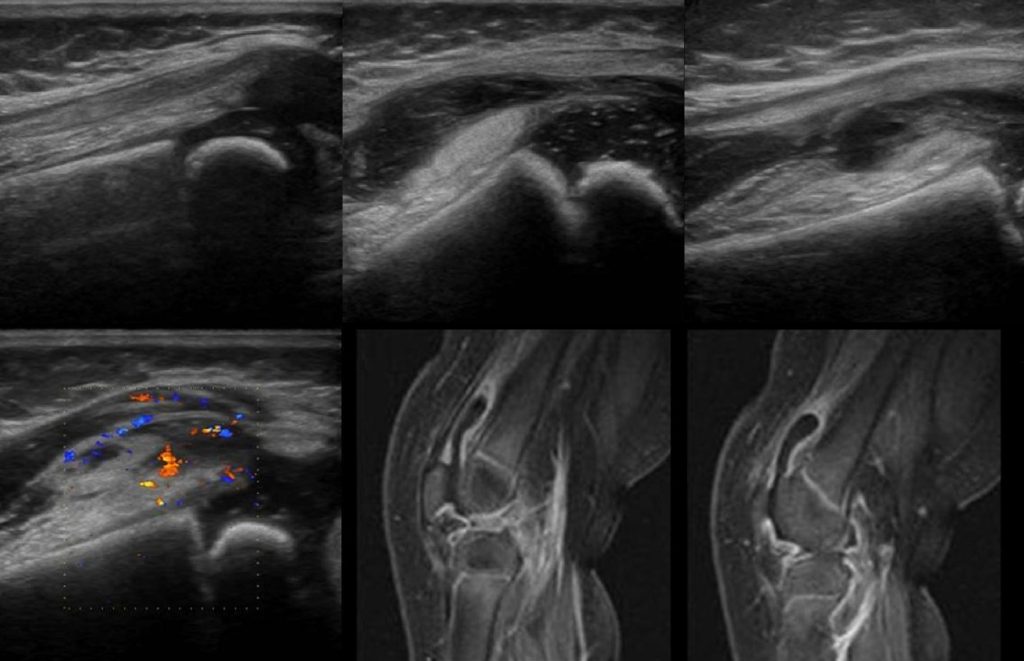

This non-invasive imaging method is essential for evaluating blood flow and detecting abnormalities in the peripheral arteries and veins.

Typically associated with the arms, legs, and neck, peripheral ultrasound uses high-frequency sound waves to provide detailed pictures of the blood arteries that are not part of the heart or brain. This method offers real-time imaging, which gives us important information about our patients’ vascular health.

The technician will gently slide the transducer, a portable instrument, over the affected region. Using sound waves that are emitted and echoes that are caught, the transducer creates real-time pictures of your blood vessels.